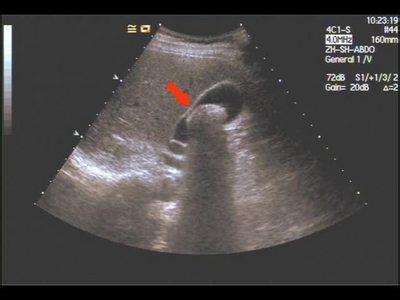

超声影像胆结石图片

胆结石图片